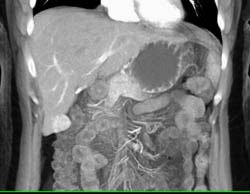

Focal Nodular Hyperplasia (FNH) Right Lobe of Liver on Multiple Phases